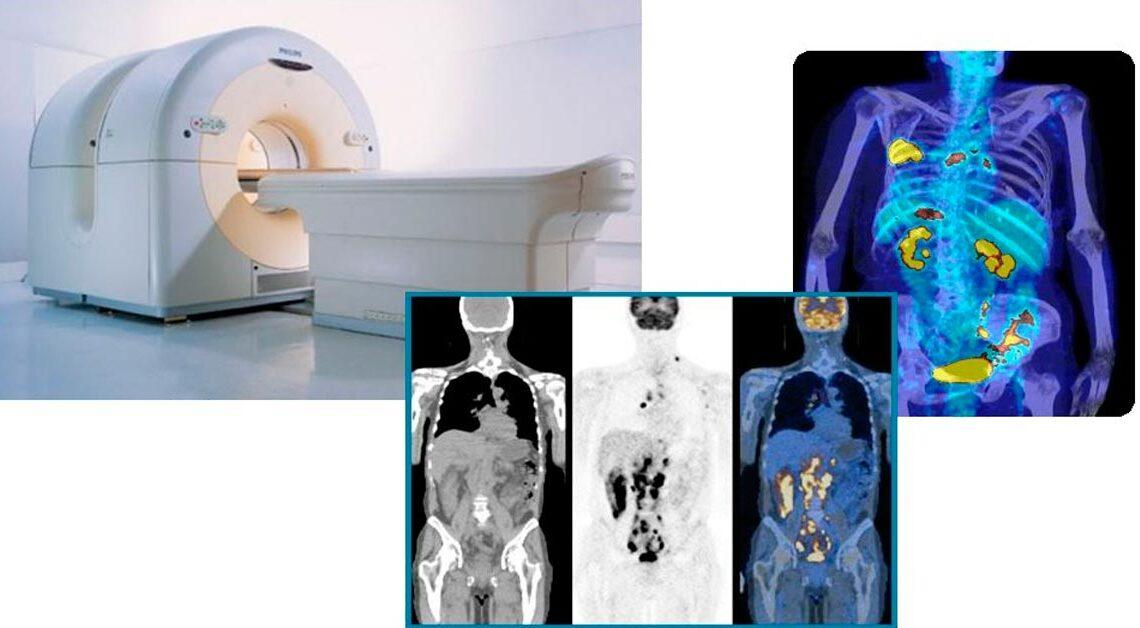

A tomografia por emissão de pósitrons, ou PET, é um procedimento popular realizado no Departamento de Medicina Nuclear.

O método de imagem mede e registra a quantidade de isótopo de rádio dentro do tecido vivo. Basicamente, PET scan fornece informações sobre a função dos órgãos e tecidos.

A tecnologia de tomografia por emissão de pósitrons é uma ferramenta vital no estadiamento e monitoramento de pacientes com câncer. Ele dá informações oncologistas e radiologistas muito importantes sobre a eficácia da quimioterapia e radioterapia.

Hoje, para fornecer aos pacientes as informações diagnósticas mais precisas, o médico pode solicitar um exame PET / CT.

A tomografia computadorizada fornece excelentes detalhes de toda a anatomia em uma representação 3D sem qualquer superposição.

A tomografia por emissão de pósitrons não é tão bom com a anatomia, no entanto, pode mostrar a função dos órgãos em grande detalhe.